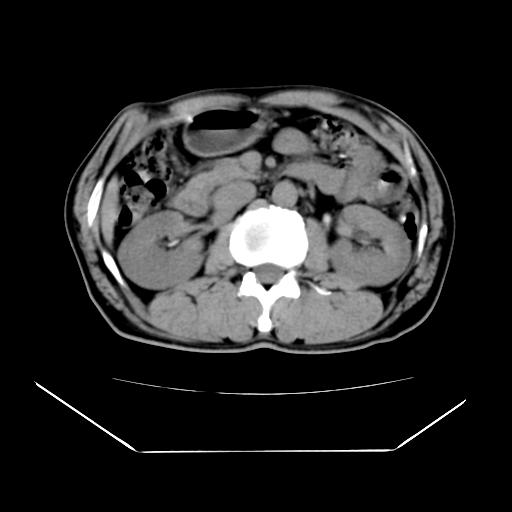

男性,55岁,外院体检afp明显升高,但b超未发现异常,否认乙肝病史。来我院ct增强。有延时扫描。

延时扫描完全充填,血管瘤

肝脏右叶动脉期可见低密度影,至延迟期被充填,考虑血管瘤可能性大。

肝右叶病灶

不排除肝右叶肝癌可能。

肝6段血管瘤

血管瘤可能性大。

是肝右静脉吧

考虑肝右静脉影。